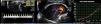

Objetivamente, apresentava-se agitada com hipotensão (73/35mmHg), taquicardia (115 bpm), hipoxémia (saturação de O2 em ar ambiente 80%) e polipneia (50 cpm). Sem sinais de trombose venosa profunda (TVP). Fez análises (hemoglobina 12,3g/dL; plaquetas 170x109/L; d-dímeros 2.962 ng/mL e troponina I 0,43 ng/mL (referência <1,50 ng/mL)) e na gasometria arterial realizada já com O2 suplementar a 5 L/min apresentava alcalose respiratória (pH 7,49; pO2 105mmHg; pCO2 28mmHg, HCO3− 20,9 mmol/L e saturação de O2 98%). Realizou eletrocardiograma (ECG), que mostrou taquicardia sinusal e sinais de sobrecarga no ventrículo direito (VD) (Figura 1) confirmados por ecocardiograma transtorácico (ETT) à cabeceira (Figura 2).

ETT (A) Plano apical de 4 câmaras telediastólico com dilatação do ventrículo direito, movimento paradoxal do septo intraventricular e PSAP estimada em 65mmHg, (B) no plano paraesternal curto-eixo com retificação diastólica do septo intraventricular em relação com hipertensão pulmonar e (C) função sistólica do ventrículo direito preservada (TAPSE 23mm).